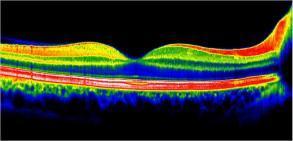

OCT maculaire

L'OCT ou Optical Coherence Tomography est une Tomographie à cohérence optique.

Il permet de dépister les maladies rétiniennes sur la zone centrale de vision nommée macula : un œdème de la rétine, des néovaisseaux, une atrophie, une membrane épi-rétinienne, un trou maculaire, une atteinte de la DMLA, du diabète, ou encore les conséquences d'une occlusion veineuse...

L’image est obtenue par l'émission d'un faisceau laser de faible énergie réalisant des images représentant des coupes des différentes couches de la rétine.